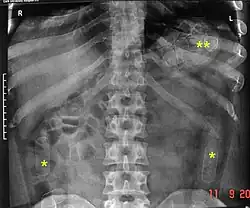

As cavity searches have proven as an ineffective strategy in the total prevention of smuggling objects as it cannot detect objects in the intestines or stomach, as well as taking into consideration the intrusive nature and inherently humiliating or degrading procedure, it has become fairly normal for authorities to instead isolate individuals in a monitored environment until they pass excreta and/or x-ray the individual's pelvic area as it is less invasive and psychologically damaging.